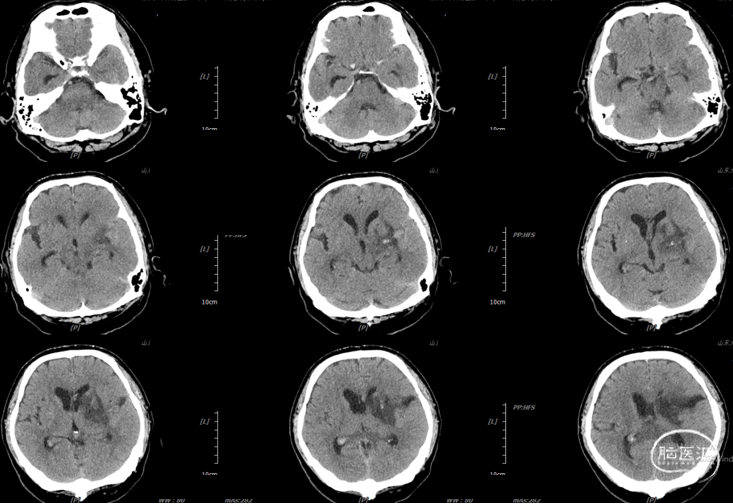

辅助检查:头胸部CT平扫2026-03-14我院脑出血并破入脑室,请结合临床复查,蛛网膜下腔出血。双肺少许纤维灶,双肺坠积性改变,请结合临床隔期复查,双肺少许小结节,考虑低危结节可能,建议结合临床年度随诊复查双肺部分小叶间隔增厚,肺水肿不除外,建议结合临床短期复查,冠脉壁钙化灶,胆囊结石。头颈部CTA2026-03-14我院颅内动脉轻度粥样硬化性改变,左侧优势型椎动脉,椎基底动脉迂曲延长。

初步诊断:1. 左侧额、岛叶、基底节脑出血破入脑室动静脉畸形?2. 脑疝;3. 高血压病3级(极高危)?4. 肺炎;5. 肺结节;6. 胆囊结石;7. 肺水肿;8. 脑动脉粥样硬化。